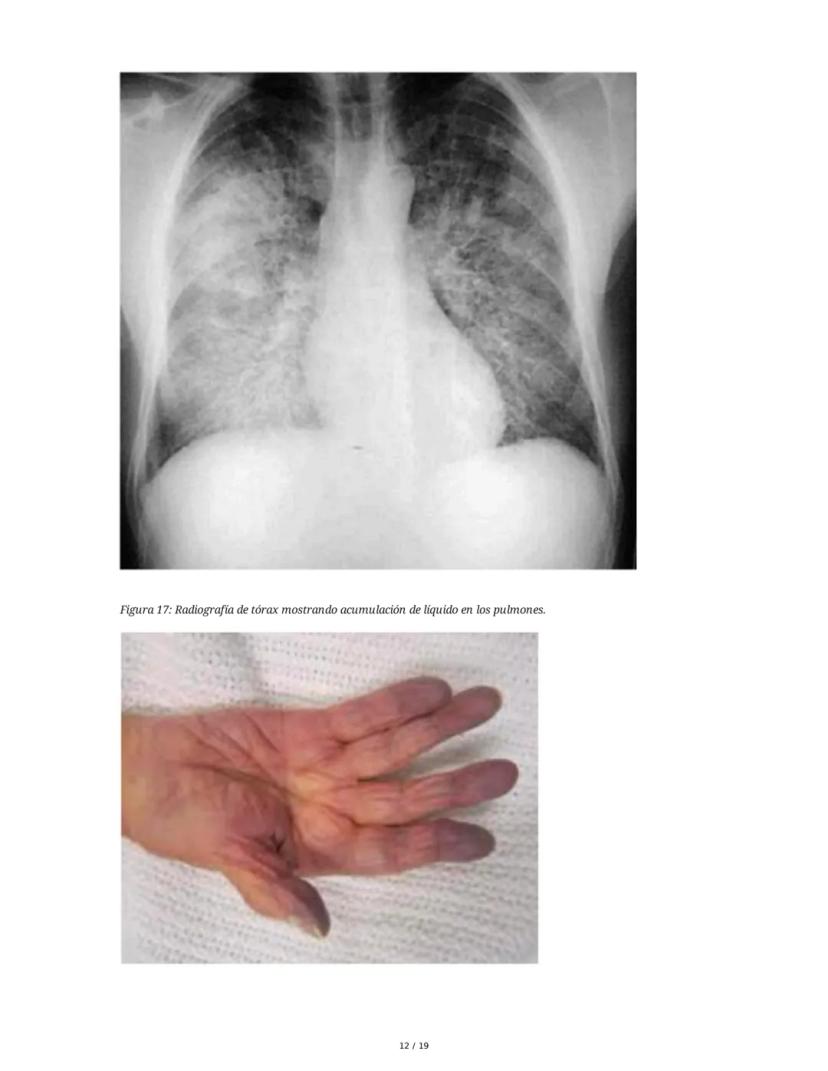

Los signos de falla izquierda incluyen llenado capilar lento, piel fría, palidez, cianosis y crépitos pulmonares. En la falla derecha encontramos ingurgitación yugular, hepatomegalia, ascitis, derrame pleural y edema maleolar.